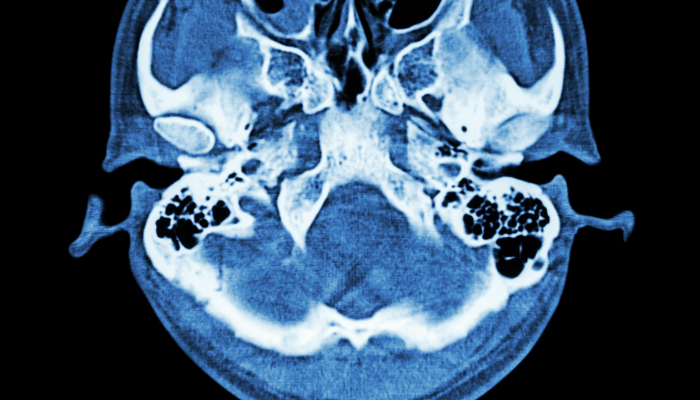

Brigham and Women's Hospital is where advanced technology and clinical research combine to provide complex neurological care and surgery.